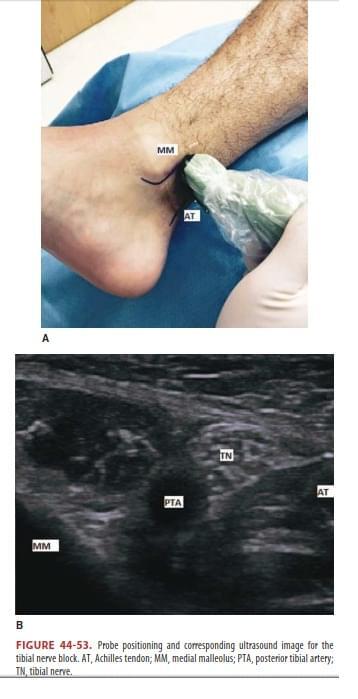

É ponto de referência anatômica para a realização do bloqueio do nervo tibial no tornozelo:

A

Maleolo medial